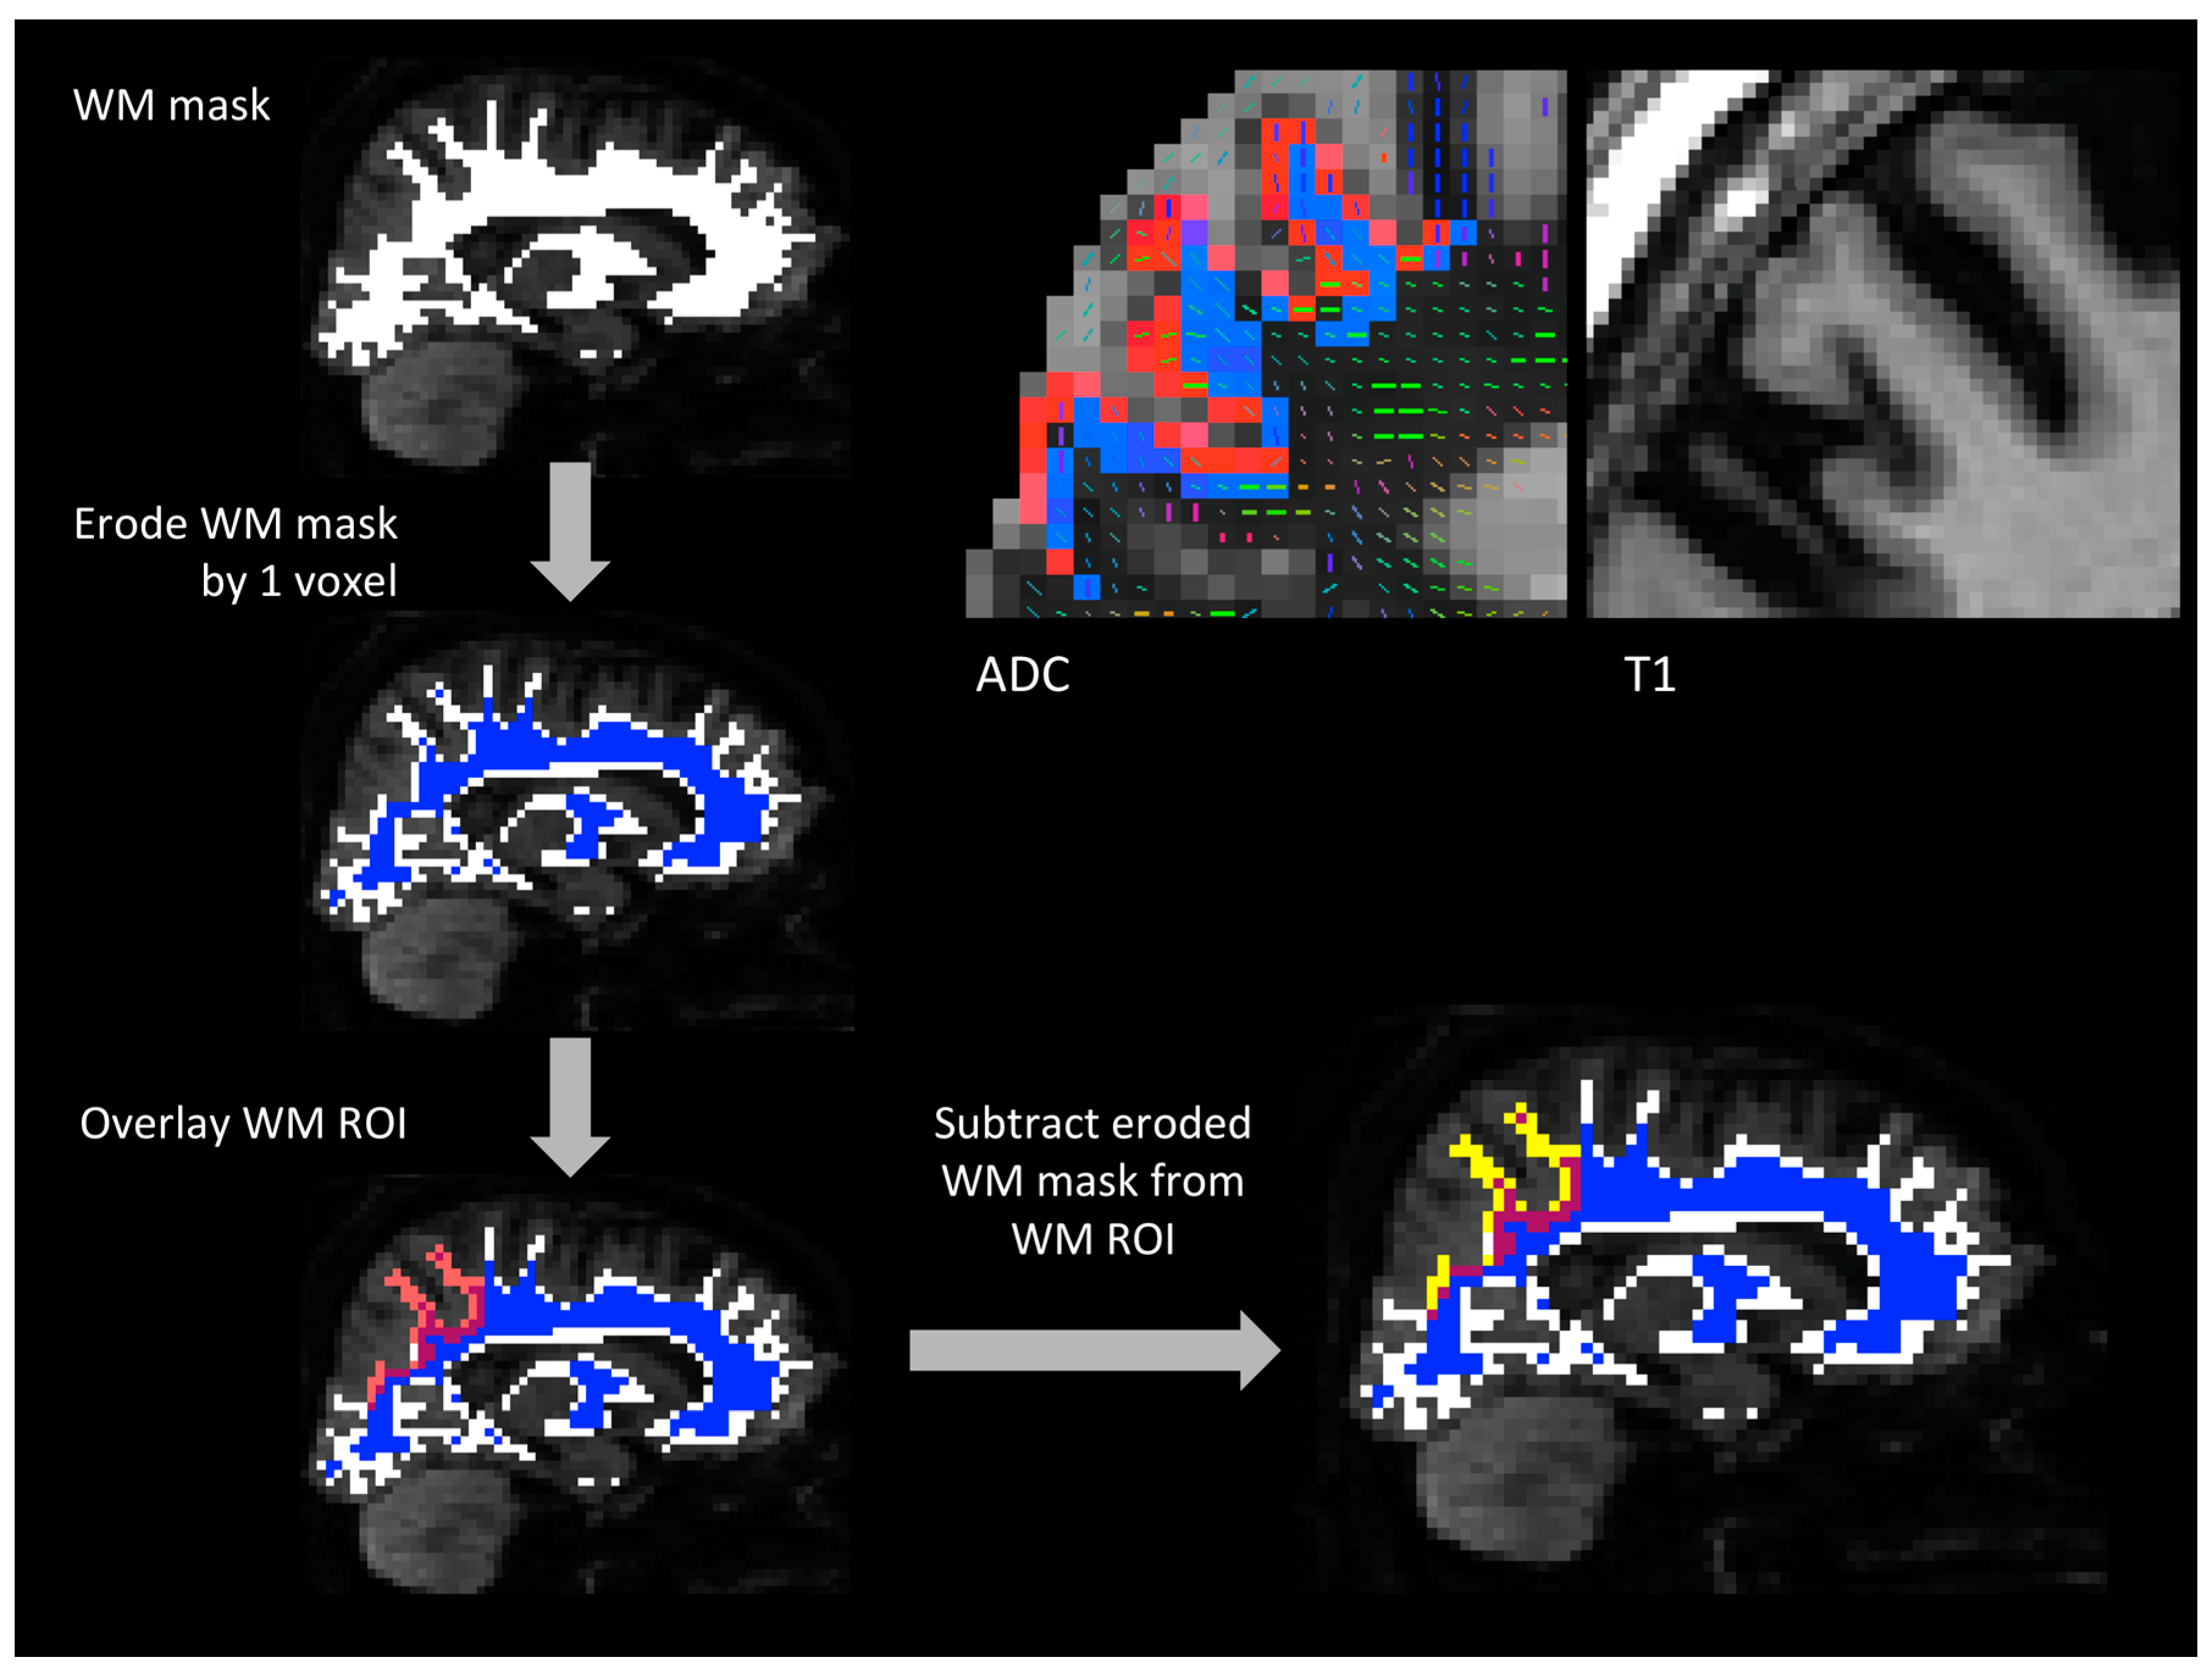

White matter (WM) ROIs were one-voxel thick and lined the white matter surface just deep to the gray matter ROIs (Figure 1). To create these WM ROIs, whole-brain cerebral white matter volumes generated in FreeSurfer were eroded by one voxel and this mask was subtracted from each white matter ROI derived from the standard FreeSurfer white matter parcellation [31]. The FreeSurfer white matter parcellation divides the entire cerebral white matter volume into 68 regions that correspond to the 68 GM regions produced in the cortical parcellation. Subtraction of the eroded cerebral white matter volume from each white matter ROI allowed the one-voxel strip of white matter just under the gray matter-white matter boundary corresponding to that ROI to be isolated. One-voxel-thick WM ROIs were chosen to minimize the seeding volume while maintaining anatomical relevance to the GM ROIs. WM ROIs were generated in T1 space and transformed into DTI space using the same methods used to transform GM ROIs. A selection of WM ROIs were overlaid onto each subject’s DTI data and visually inspected prior to fiber tracking.

Figure 1.

Generating WM ROIs. (top left) one subject’s white matter mask overlaid on that subject’s diffusion-weighted MRI data. The WM mask was eroded by one voxel and the resulting mask is shown in blue. Then, WM ROIs generated in FreeSurfer and transformed into diffusion space (one example shown in transparent red) were overlaid on the eroded WM mask. The eroded WM mask was subtracted from each WM ROI to isolate the strip of voxels just deep to the GM/WM interface that was used as the final WM ROI (shown in yellow). (top right) one subject’s left superior parietal cortex GM ROI (red) and WM ROI (blue) overlaid on an apparent diffusion coefficient (ADC) map. The corresponding region on that subject’s T1-weighted image is shown on the far right. GM and WM ROIs were transformed from T1 space to DTI space using bbregister, which relies on the gray matter-white matter boundary for image alignment. The bright voxels lining the GM ROI are CSF and the dark voxels deep to the WM ROI are white matter. On the left, the primary diffusion direction of each voxel is visible and the map is thresholded at FA = 0.1. In this section, a greater number of WM voxels survive the FA threshold compared to the voxels in the GM ROI (voxels that survive the FA threshold have a diffusion tensor in them). CSF: cerebrospinal fluid, DTI: diffusion tensor imaging, FA: fractional anisotropy, GM: gray matter, MRI: magnetic resonance imaging, ROIs: regions of interest, WM: white matter.